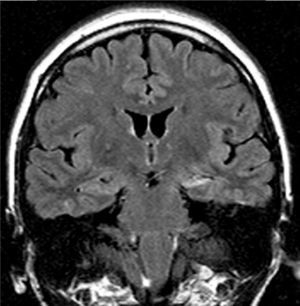

Los hallazgos en las IRM se pueden observar en las figuras 1–8. Se observa predominancia en el diagnóstico de esclerosis del hipocampo en los pacientes con epilepsia temporal, tanto en el grupo de enfermos respondedores como no respondedores. En la epilepsia extratemporal se observa con mayor frecuencia la presencia de malformaciones del desarrollo cortical y/o tumores, que fueron consideradas en el mismo grupo debido a que estas lesiones muchas veces resultan indistinguibles unas de otras a través de las IRM. Esta predominancia se observa más acentuada en el grupo de enfermos resistentes al tratamiento.